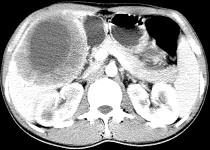

问题 女,61岁,上腹部疼痛一个月,食欲减退,消瘦,CT所见如图,最可能的诊断是 ( )

选项 A.肝脓肿 B.肝转移瘤 C.胃癌肝转移 D.肝包虫病 E.原发性肝癌

答案 C